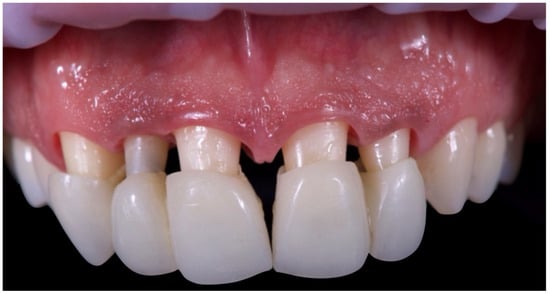

The first set of provisional restorations (Figure 10) was cemented using a non-eugenol temporary luting agent (Temp-Bond™ Clear, Kerr Dental, 8302 Kloten, Switzerland).

Figure 10. First provisional restoration.

These provisionals were segmented into two units (right and left) and maintained the existing interincisal diastema. The deep overbite was corrected, and an appropriate incisal guide was established. Both provisional restorations were progressively modified every 2–3 weeks to promote soft tissue adaptation, manage the emergence profile, and support the re-establishment of a new prosthetic cementoenamel junction (CEJ) over time. This approach also allowed for the continuous evaluation of the patient’s phonetics and functional dynamics. Approximately four months later, the preparations were refined under 16× magnification to optimise the emergence profiles and support soft tissue conditioning while preserving the edgeless finish line to enhance papillary stability and control (Figure 11).

The second provisional restorations (Figure 12) were luted using zinc phosphate cement (Harvard) and mixed with petroleum jelly to facilitate later removal. At this stage, the interincisal diastema was closed. During the second provisional phase, tooth 1.2 developed symptoms of thermal sensitivity and mild pain, necessitating endodontic treatment.

Figure 12. Second provisional restoration.